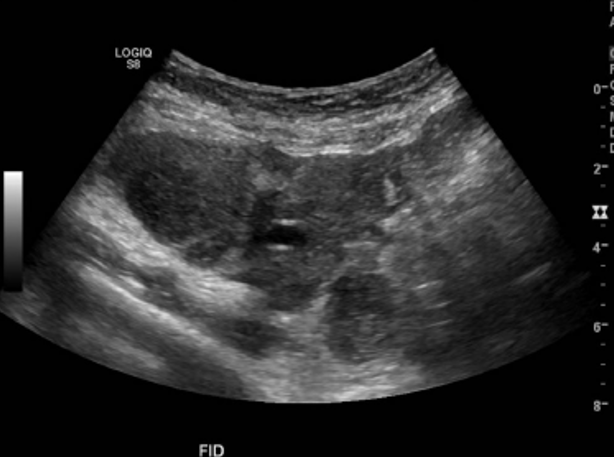

En la cavidad abdominal, en el área de la FID se aprecia una gran masa alargada y hipoecogénica multifocal, que ocupa todo el flanco y la fosa ilíaca derecha y que mide al menos 20 cm en sentido longitudinal, siguiendo la dirección del colon.

Impresión diagnóstica: Extensa lesión de tipo neoplásico con compromiso mesentérico e intestinal lateralizado a derecha

Adenopatías retroperitoneales y mesentéricas.

Podría tener un origen linfoproliferativo por el compromiso retroperitoneal, el compromiso del bazo y la ausencia de compromiso hepático.